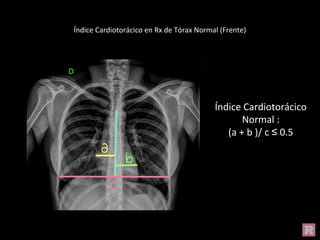

Índice Cardiotorácico en Rx de Tórax Normal (Frente)

Índice Cardiotorácico

Normal :

(a + b )/ c ≤ 0.5